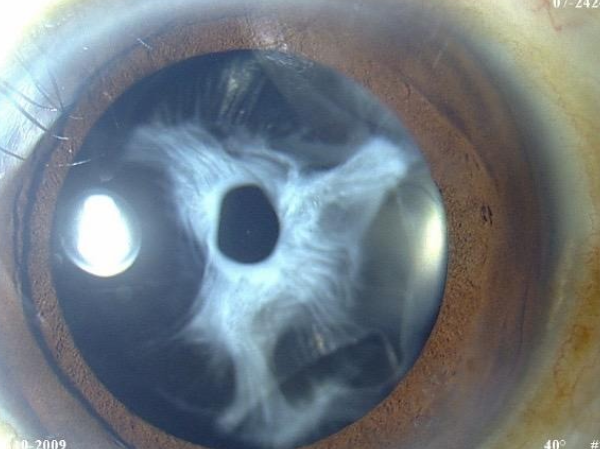

Difficult Cataract Surgeries : Posterior Polar Cataract

Posterior polar cataract pre operative eye condition in Trivandrum

Pre-Operative